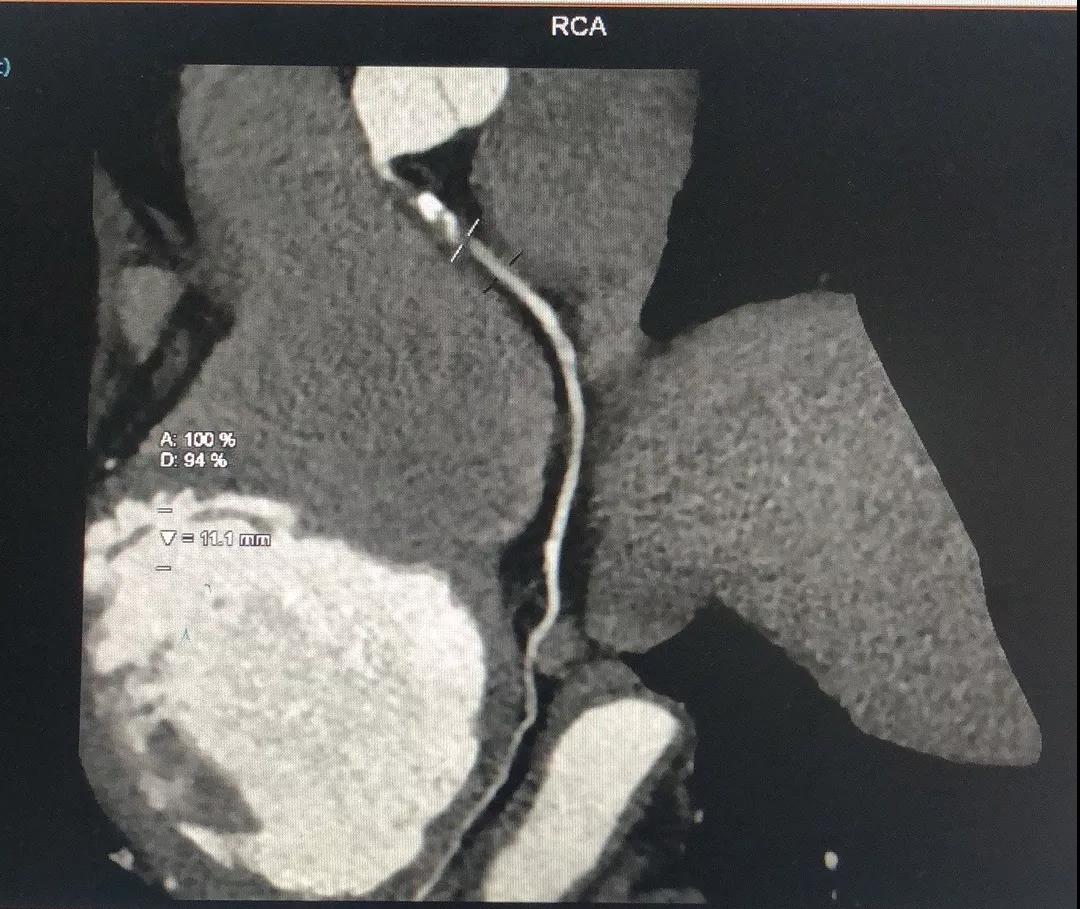

关于RCA

RCA CTA特点

1、入口清楚;

2、闭塞段长度小于20cm;

3、闭塞段血管无明显扭曲;

4、闭塞段内有两处明显的钙化斑块;

5、闭塞出口处血管相对比较“健康”;

6、侧枝血管汇入左室后支;

7、后三叉处的血管相对比较“健康”。

有了上述信息,再结合冠脉造影资料,开通RCA就有了比较清晰的思路:

1、逆向导丝抵达闭塞出口,Fielder系列引导,迅速交换CP或Gaia3导丝逆向进攻;

2、灵活使用Knucle技术;

3、前向CP或Gaia3导丝正向准备;

4、正逆向导丝交汇/无限接近;

5、Re-Cart,Kissing Wire,AGT;

6、IVUS评估和优化支架植入。